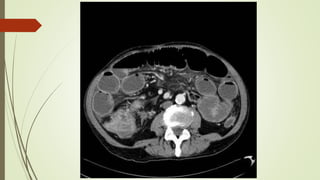

IN PLAIN XRAY

Dilated bowel loops

 small bowel > 3 cm

 Proximal large bowel > 9 cm

 Transverse colon > 5.5 cm

 Sigmoid colon > 5 cm

Multiple air fluid level

step ladder pattern

Jejunum : Valvulae conniventes - concertina or ladder effect

Ileum : featureless

Colon : Haustral folds

IMAGING IN PLAIN XRAY Dilatedbowel loops  small bowel > 3 cm  Proximal large bowel > 9 cm  Transverse colon > 5.5 cm  Sigmoid colon > 5 cm Multiple air fluid level step ladder pattern Jejunum : Valvulae conniventes - concertina or ladder effect Ileum : featureless Colon : Haustral folds